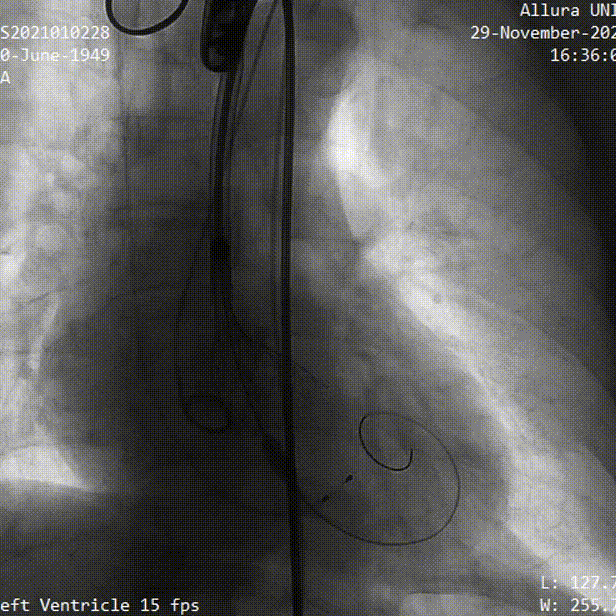

主动脉根部造影

23mm球囊预扩

瓣膜定位

瓣膜释放

球囊后扩

术后造影